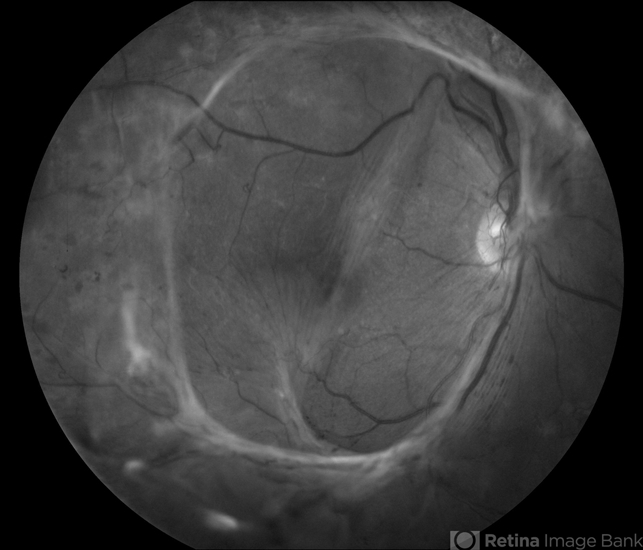

- Proliferative Diabetic Retinopathy

- tractional retinal detachment, fibrous proliferation

- Young female patient with severe diabetes. Patients VA is 20/400 in the right eye. Fundus photos show a lot of fibrosis traction throughout the macula area. Fovea seems flat. Patient will undergo surgery for peeling of traction.